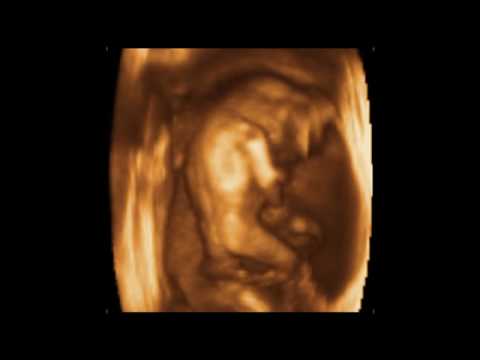

Con la ayuda de la prueba de detección neurológica prenatal con ultrasonido 4D (Wolf prenatal Neurological Test-KANET), que fue desarrollada con el objetivo de evaluar los patrones de movimiento y comportamiento fetal, se puede estimar el desarrollo funcional del sistema nervioso central (SNC) ( 45, 46). La prueba analiza el comportamiento del feto con especial énfasis en los movimientos faciales y las características cualitativas del movimiento (Figura (Figura 3).3). En KANET se incorporan también el signo de daño cerebral de pruebas neurológicas neonatales de Amiel-Tisson, suturas superpuestas de cráneo y pulgar neurológico (46).

Ecografía 4D que muestra algunos de los parámetros KANET: movimientos faciales, anteflexión de la cabeza, apertura de la boca, movimiento de la mano a la cara, posición normal del pulgar y movimientos de los dedos, expulsión de la lengua.